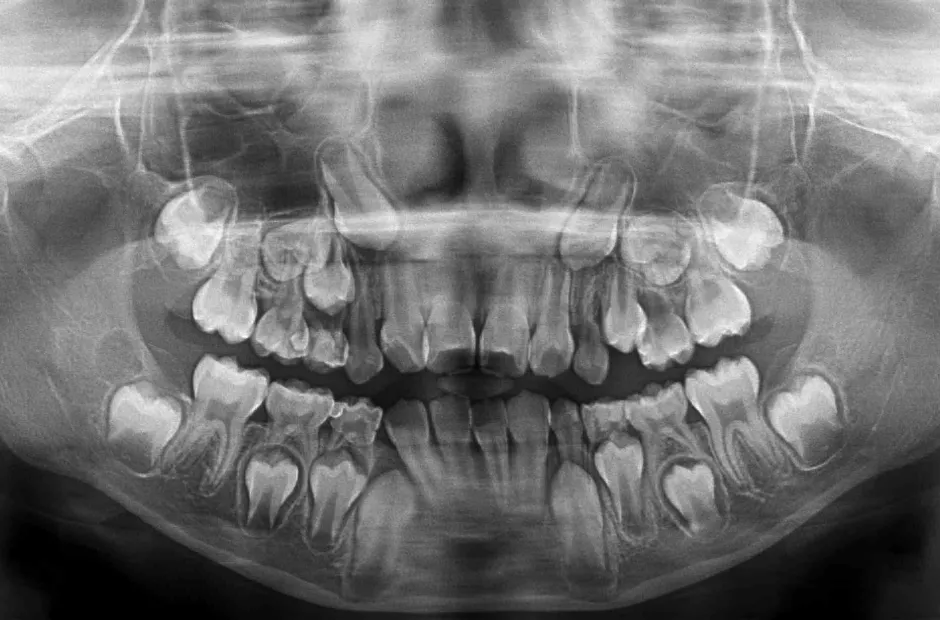

精密検査

口腔内写真やレントゲンの撮影、歯型取りなど、口や顎の状態を詳しく把握するための精密検査を行ないます。さらに、骨の成長状況や身長・体重の増加傾向、永久歯の生えかわりについても確認します。

先天的な歯や顎の症状

先天的な歯や顎の異常や疾患には、顎変形症や埋伏歯、過剰歯、先天性欠如などがあります。これらの異常や疾患に対し、子どもの時期から適切な処置や矯正治療で歯と顎の発育を正しい方向に導くことができると、将来の大掛かりな治療や外科手術を回避しやすくなります。歯や顎のことで気になることがあれば、お気軽にご相談ください。

永久歯が生えてこない(埋伏歯)

何らかの原因で永久歯が正常に生えることができず、歯肉に埋もれたままになる歯のことを埋伏歯といいます。この歯を放置すると、隣の歯根を吸収してしまうことがあるため、早めの治療が必要です。埋伏歯を早期に発見できると、抜歯せずに矯正治療で正常な位置に戻せる可能性が高くなります。これは、小児矯正では、顎の成長を促進して歯が正しく並ぶスペースを作ることができるからです。そのため、乳歯が永久歯に生え変わり始めるころに一度受診し、埋伏歯の有無を確認することが大切です。

埋伏歯がある場合は、矯正装置を使って歯列を拡げ、必要に応じて開窓術や牽引を行なって埋もれた歯を正しい位置に引き上げます。すでに永久歯が生えそろっていても、適切な治療を受けることで抜歯せずに改善できる場合もあるので、気になることがあれば早めにご相談ください。

3歯以上埋伏歯がある場合は、矯正治療が保険適用になります。

永久歯の数が足りない

(先天性欠如)

先天的に永久歯が不足している状態を先天性欠如といいます。先天性欠如があると、すきっ歯になったり、乳歯が抜けずにそのまま残ったりすることがあります。すきっ歯の場合は、矯正治療ですき間を閉じることで、将来的にブリッジやインプラント、入れ歯が必要になる事態を回避できる可能性があります。歯科検診で指摘されるまで気づかれないことが多く、放置すると高確率で歯並びや噛み合わせに悪影響を及ぼします。調査によると、先天性欠如歯は10人に1人の割合で見られ、近年増加傾向にあります。

6本以上永久歯が無い方は、矯正歯科治療が保険適用になります。

歯が多い(過剰歯)

通常、永久歯は親知らずを含めて32本ありますが、過剰歯とはその数を超えて余分に歯が生えている状態を指します。過剰歯が歯肉の中に埋まっていて、向きが悪くほかの歯に害を及ぼしている場合には抜歯が必要です。しかし、問題がなければそのまま経過を見守ることもあります。